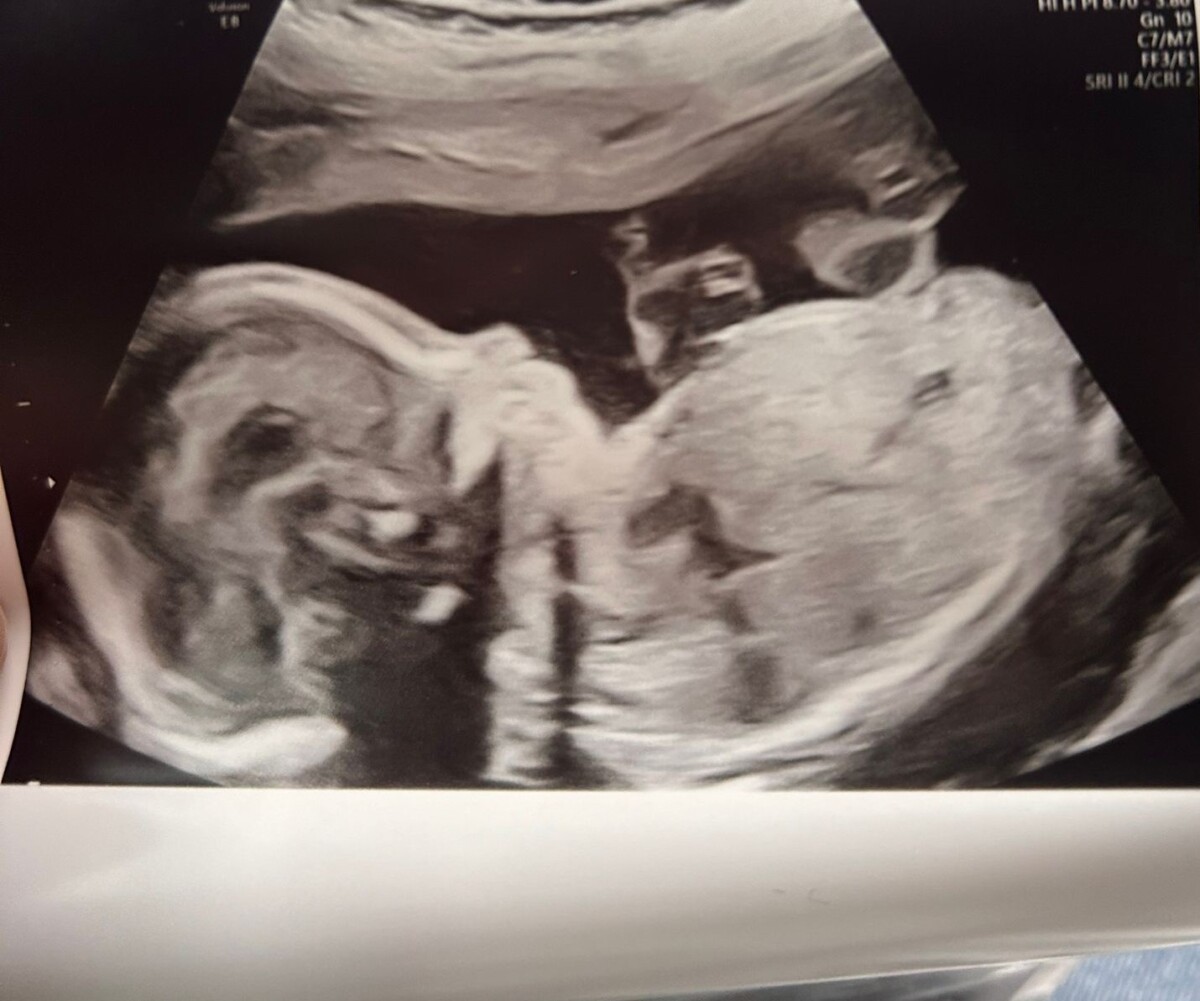

baby in womb